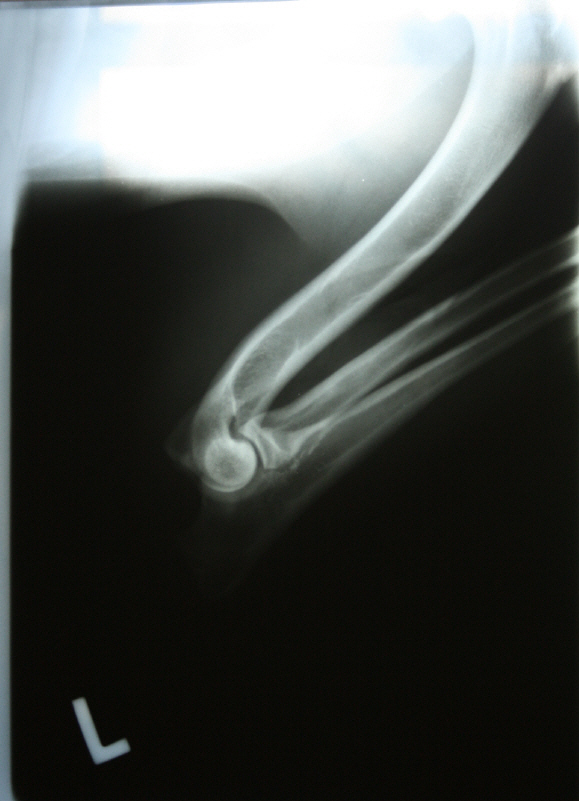

Allys linker Ellbogen gebeugt Allys rechter Ellbogen gebeugt